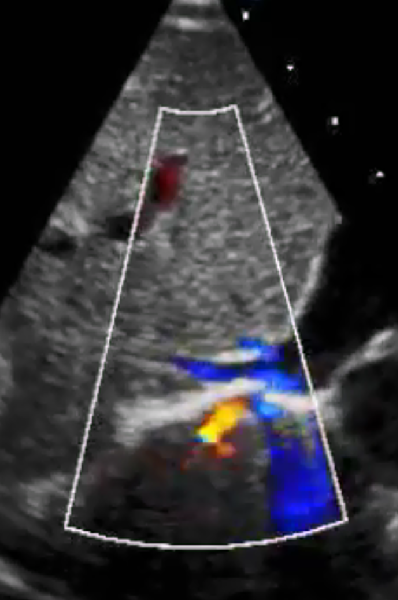

经胸超声心动图

2021-12-20

8